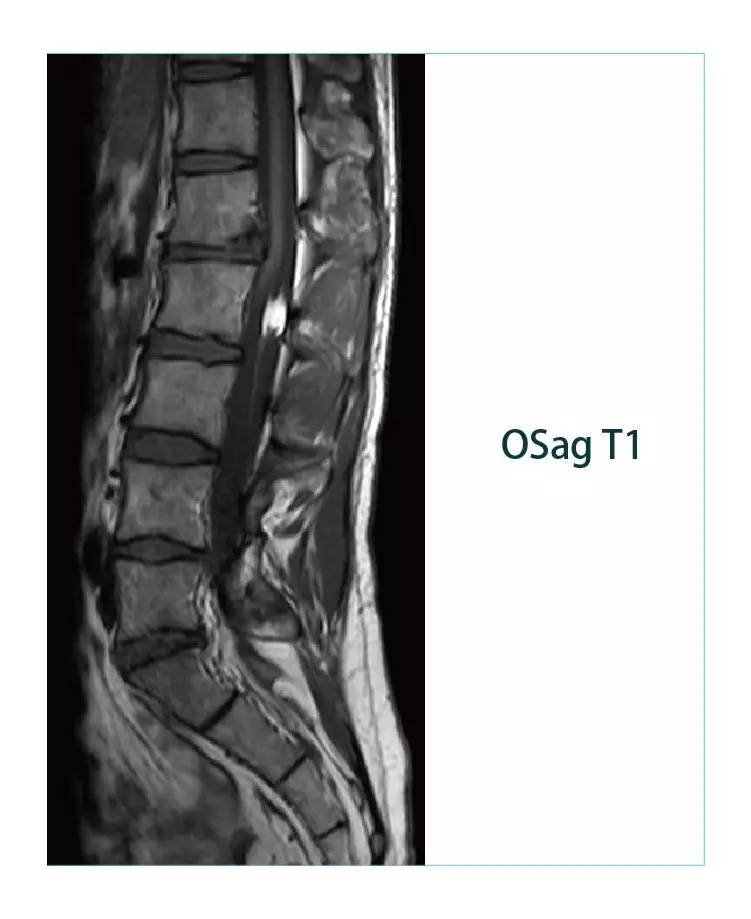

【朗润影像档案】磁共振影像病例分享(编号20190225)

1551142369809397.jpg1551142384228370.jpg